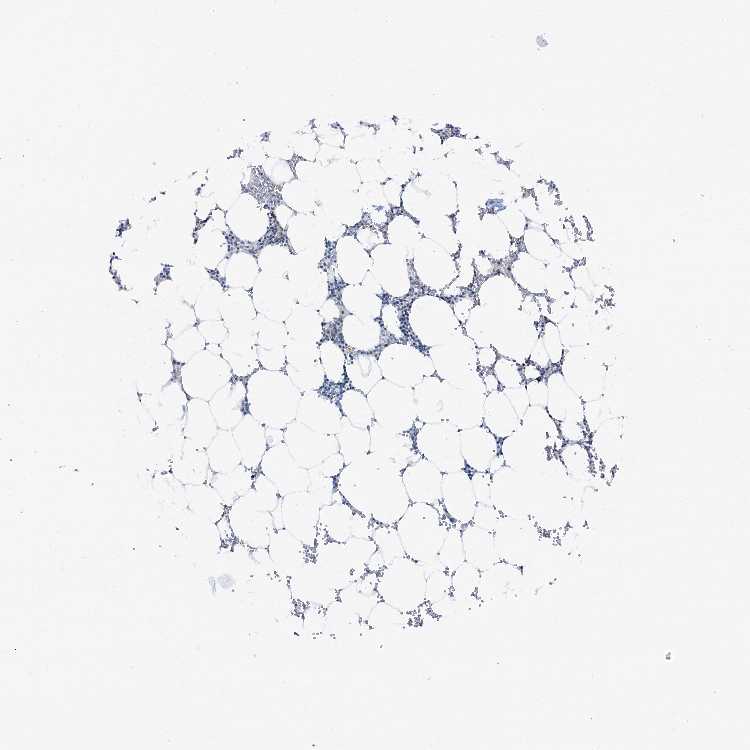

BONE MARROW - Antibody stainingi

Antibody staining in the annotated cell types in the current human tissue is reported as not detected, low, medium, or high, based on conventional immunohistochemistry profiling in selected tissues. This score is based on the combination of the staining intensity and fraction of stained cells.

Each image is clickable and will lead to virtual microscopy that enables deeper exploration of all samples and also displays staining intensity scores, fraction scores and subcellular localization as well as patient and tissue information for each sample.

Antibody HPA038672Antibody HPA038673Antibody CAB034319

Hematopoietic cells LowNot detectedNot detected